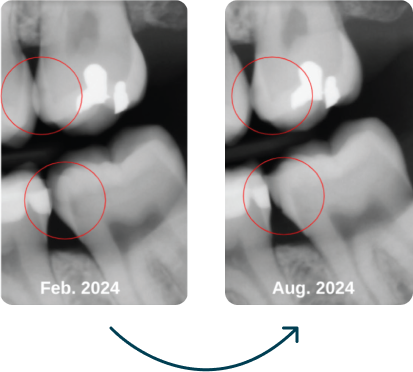

“In february of this year we took bitewings on this patient and diagnosed a need for fillings on #15-MO and 10-MO. Due to life circumstances, the patient did not return for her restorative appointment. She did start using Dr. Jen’s superpaste at that time due to high caries risk. She returned in August for her next hygiene appointment and we decided to take bitewings again to see how far the decay had progressed. I was blown away at the new images!! I wish I had a video of the doctor doing the exam, looking at #18 on the radiograph, checking the patients mouth, going back to the radiograph again, leaning back and pondering everything he knows about remineralization.”

April C. , RDH